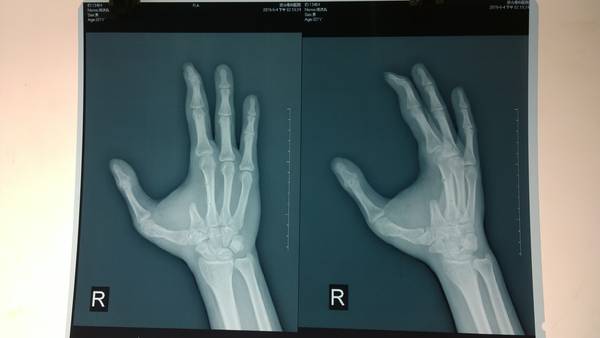

[手指再造] 残指重建拇指

今天上传术中及近期术后的图片